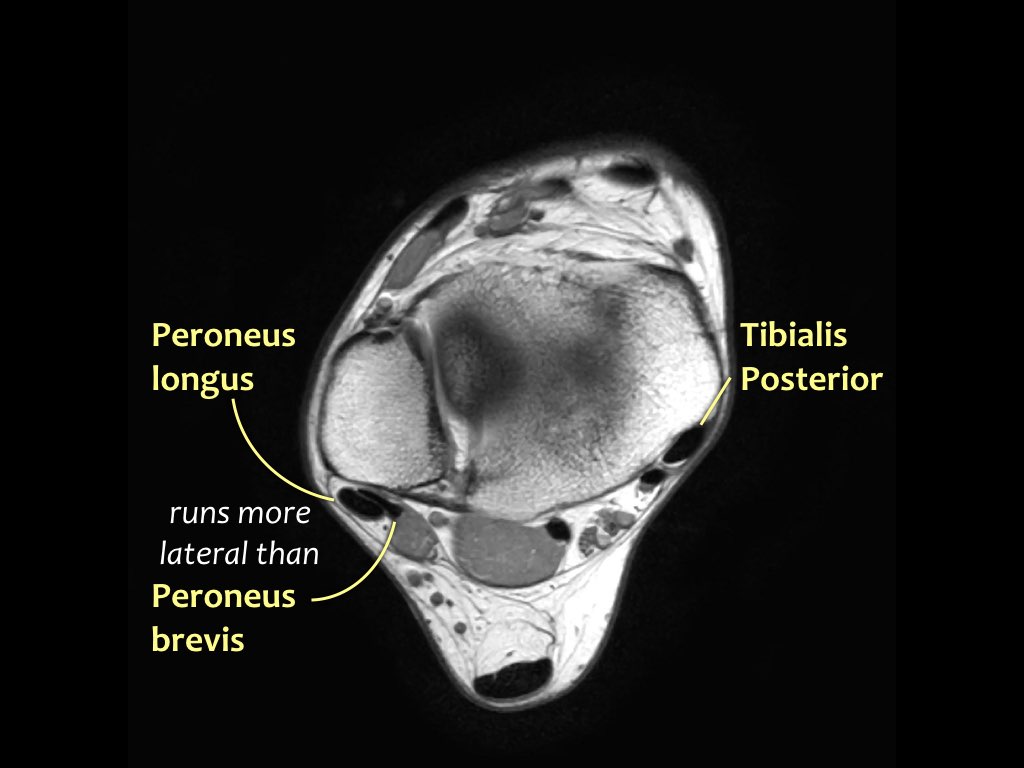

Giải phẫu trên mặt phẳng cắt ngang

Các gân có thể được chia thành bốn khoang:

- Khoang ngoài

- Gân cơ mác dài (Peroneus Longus)

- Gân cơ mác ngắn (Peroneus Brevis)

- Khoang trong (từ trong ra ngoài: Tom-Dick-Harry)

- Gân cơ chày sau (Tibialis Posterior – PTT)